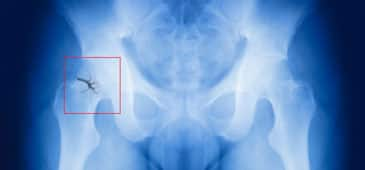

Three months of vitamin D supplementation improves survival among hip fracture patients April 07 2017. The April 2017 issue of The Journal of Nutrition Health & Aging published the results of a randomized, placebo-controlled trial that found improved survival among hip fracture patients with osteoporosis who were treated with vitamin D.

The trial included 88 men and women aged 50 and older admitted for surgery for an acute osteoporotic hip fracture. Participants received standard treatment for osteoporosis, which consisted of daily calcium carbonate, vitamin D3, a bisphosphonate drug and rehabilitation for three months. At the end of this period, the subjects were randomized into groups that received a single dose of calcifediol (25-hydroxyvitamin D) plus instruction concerning specific hip exercises, or a placebo in addition to recommendations to engage in physical activity and muscle strengthening to prevent falls. Vitamin D and the placebo were administered again at 6, 9 and 12 months.

A year after their surgeries, one participant who received vitamin D plus exercise recommendations and nine members of the nonintervention group had died. At four years, 93% of the vitamin D group had survived compared with 62% of those who did not receive the vitamin. The latter group also had more medical complications noted at the second and third visits.

“To our knowledge, this is the first study to assess survival in patients who were treated with high doses of vitamin D (calcifediol) and daily exercise after surgery for an osteoporotic hip fracture,” announce Ana Laiz and colleagues.

“We found a single 3 mg dose of calcifediol administered orally once every three months over one year can be effective in improving survival in patients after surgery for acute hip fracture,” they conclude. “The effect of physical exercise added to calcifediol remains to be confirmed, due to the poor adherence to the nonpharmacological treatment.”